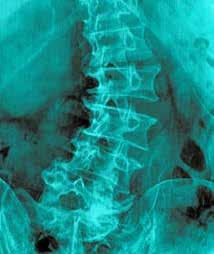

Early onset scoliosis (EOS) is an abnormal sideways curve or deformity of the spine, often in the shape of an “S” or a “C,” found in patients under the age of ten years. The cause of EOS is multifactorial. Sometimes, it develops in patients for an unknown reason; these patients are said to have idiopathic infantile scoliosis. Other patients could have suffered improper spinal development in utero and have a condition referred to as congenital scoliosis. A patient could also have a neuromuscular condition such as cerebral palsy, or a spinal cord injury that led to the deformity known as neuromuscular scoliosis.

Syndromes like Marfans or Prader-Willi are also associated with EOS patients: these patients are said to have syndromic scoliosis. Karol et al. studied early definitive spinal fusion in which the spines of EOS patients are straightened and fused in place, and found that patients required at least 22 cm of thoracic height for adequate ventilation1. Unfortunately, early fusion of the thoracic spine led to a loss of thoracic height, totaling just 10 cm of growth in some patients. Those patients suffered severely diminished lung functionality. To fight back against the negative consequences of early definitive fusion, Dr. Robert Campbell developed innovative treatment options. In 1988, Dr. Campbell used his vertical expandable prosthetic titanium rib (VEPTR) as a treatment for congenital forms of EOS to improve the deformity and allow for growth of the developing spine. The VEPTR prosthesis became the first long-term adjustable implant utilized that led to “growth-friendly” surgical treatments for EOS patients2. Growth-friendly treatments include VEPTR growing rods, curved metal rods that are surgically attached to the spine, ribs or pelvis and are lengthened over a period of time. Growing rods are utilized to avoid and treat thoracic insufficiency syndrome, a condition that occurs when the chest is incapable of supporting sufficient breathing due to chest deformity. The growing rods allow for some spinal correction as the patient grows and matures. Due to these revelations, practitioners shifted to implementing procedures that delay spinal fusion.

EOS patients have varying degrees of physical impairment, such as underlying medical conditions, severity of spine curvature and chest-wall deformity that should be considered when determining interventional therapy. Patients with Adolescent Idiopathic Scoliosis (AIS) face similar issues when it comes to abnormal curvature of the spine. A major difference between EOS and AIS is that AIS does not manifest until late childhood, older than ten years of age, or adolescence. AIS appears through the onset of puberty as a child grows rapidly during this time. Much like EOS patients, the AIS population with larger curve-deformity magnitudes also has compromised pulmonary function3,4,5. Posterior spinal fusion (PSF) is a surgical procedure that is often utilized in the treatment of AIS. This operation works in a twofold manner. It offers correction to the abnormal spine curvature, as well as prevents future spinal curve progression.